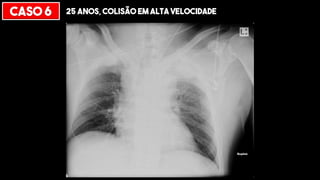

CASO 6 25 ANOS, COLISÃO EM ALTA VELOCIDADE

“APICAL CAPPING”

HEMATOMA MEDIASTINAL

> 8 cm

Traqueia desviada

Mediastino

alargado